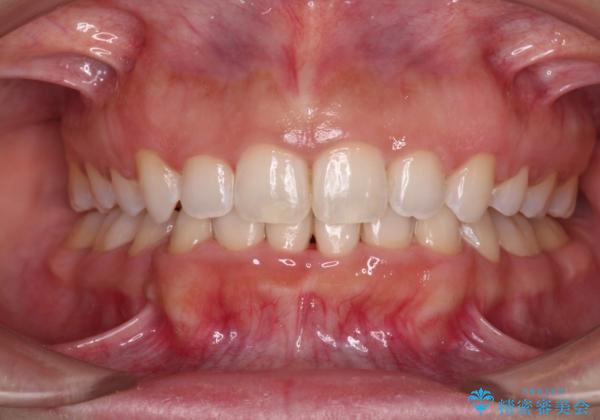

口がしっかりと閉じられない ワイヤー装置での抜歯矯正で出っ歯を改善

- 口元の突出感と口の閉じにくさを気にして来院された患者様です。

上下左右の小臼歯4本を抜歯し、ワイヤー装置にて口元を引っ込めるよう矯正治療を行うこととしました。

上下顎ともに前突しており、特に上顎は著しい突出感でした。

また、下顎歯列には左右差があり、非対称な抜歯が必要と判断されたため、治療は困難なものとなりました。

それでも根気強く通院してくださり、横からの顔貌の印象が大きく改善され、スムーズに口が閉じられるようになりました。